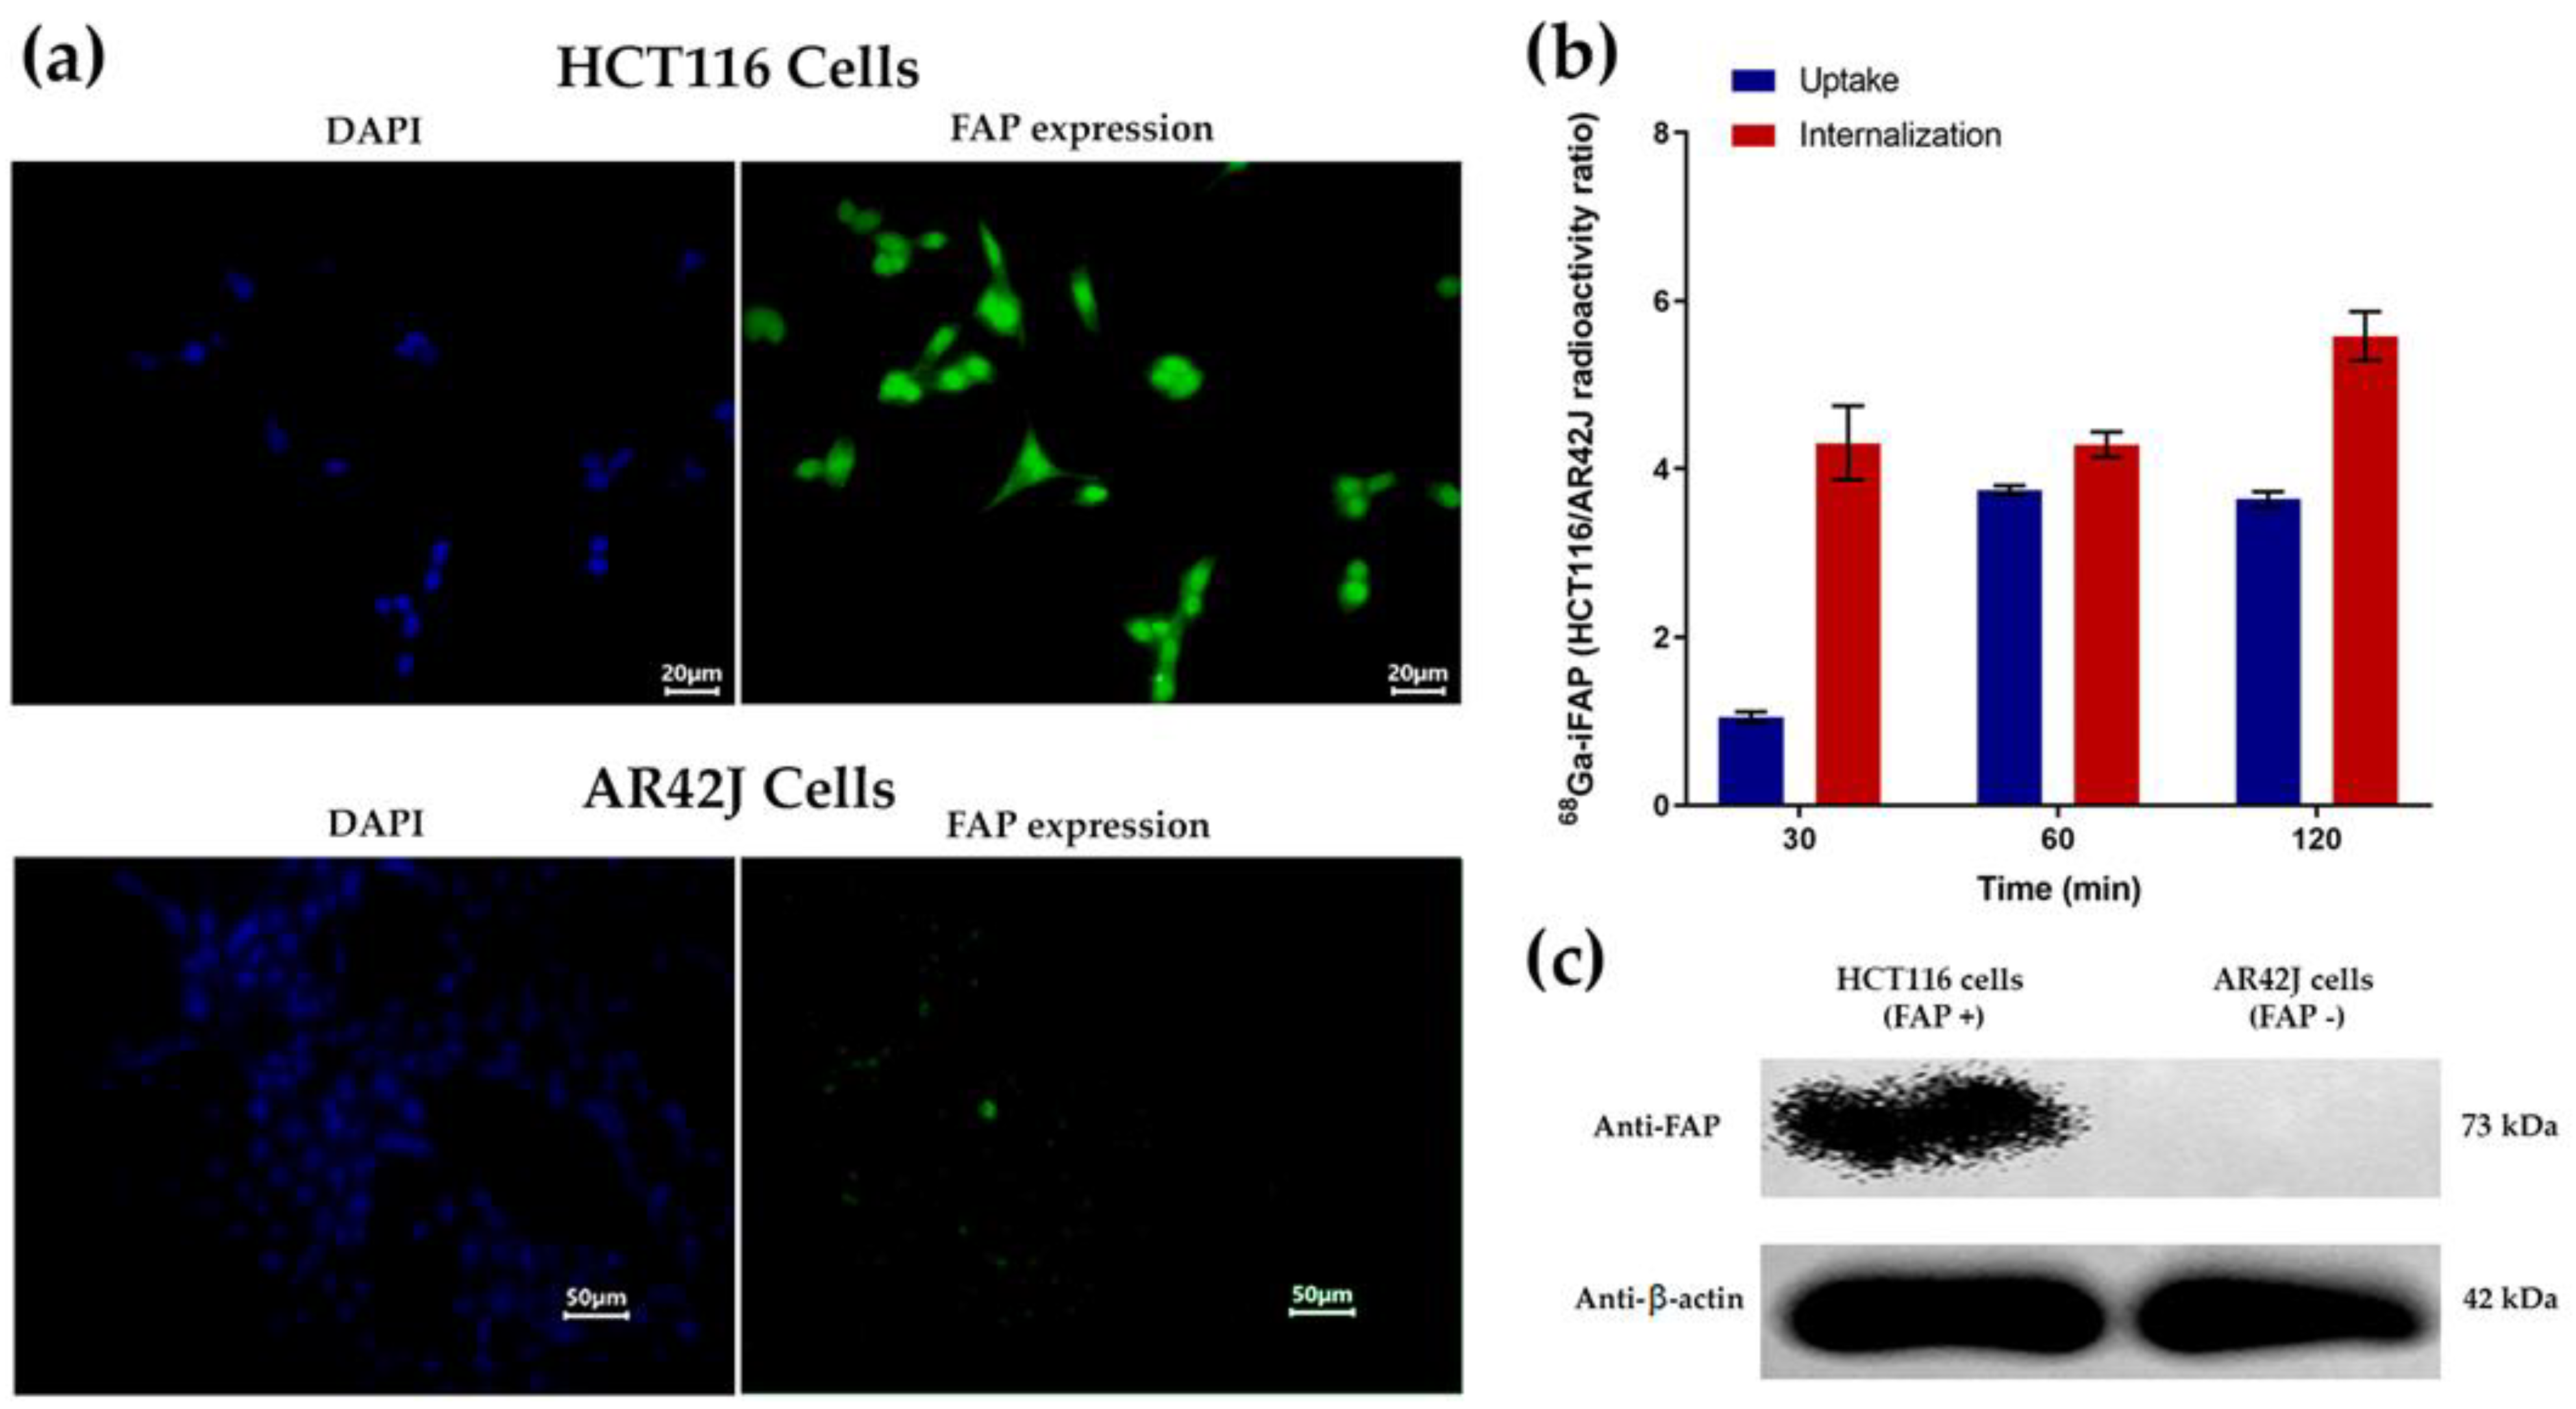

3.4.2. Immunofluorescence, Western Blot, Cellular Uptake, and Internalization